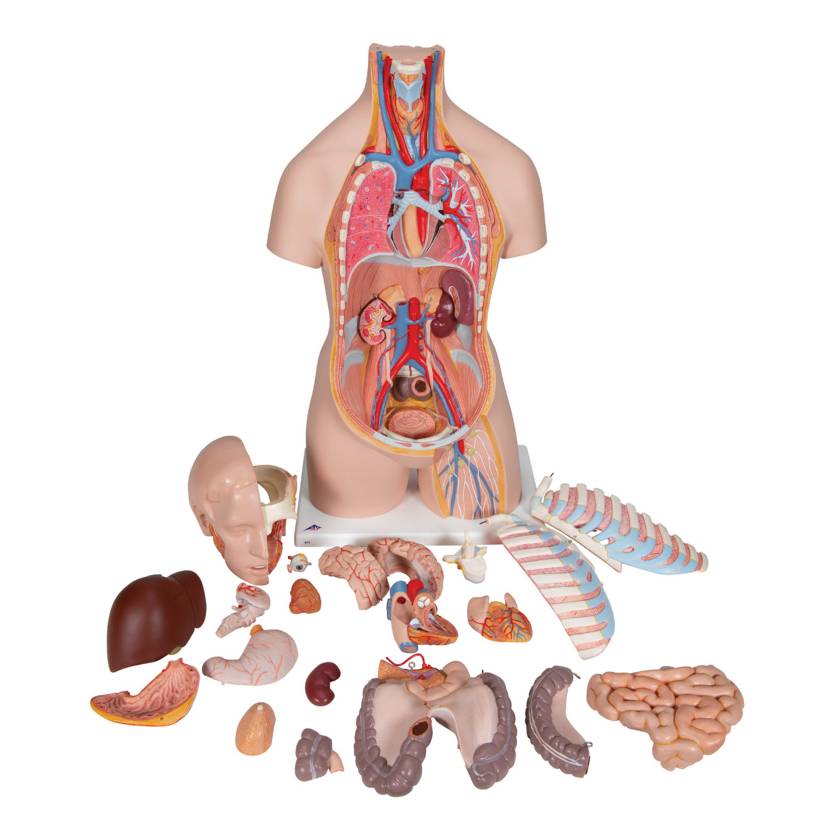

The detailed design of this 21-Part Classic Unisex Torso with Head & Open Back Model is ideal for teaching, medical training, and explaining anatomy to patients. This excellent educational tool makes learning the location of organs and understanding system anatomy easy.

Features:

- Unique open neck and back section from the cerebellum to the coccyx

- Showing vertebrae, intervertebral discs, spinal cord, spinal nerves, vertebral arteries, and many other features represented in detail

- 21‑part anatomically accurate unisex torso designed for high‑quality educational use

- Hand‑painted details and durable plastic construction for long‑lasting classroom or clinical demonstration

- All organs are hand‑painted, making structures easy to identify and learn

- Supplied with the following removable components:

- 7th thoracic vertebra removable

- 6-part head

- 2-part stomach

- Lungs

- 2-part heart

- Liver/gall bladder

- 4-part intestine

- Kidney half

- Bladder half

- Open back

- Brain

- Product Dimensions: 34.3" x 15" x 9.8"

- Product Weight: 21.15 lbs